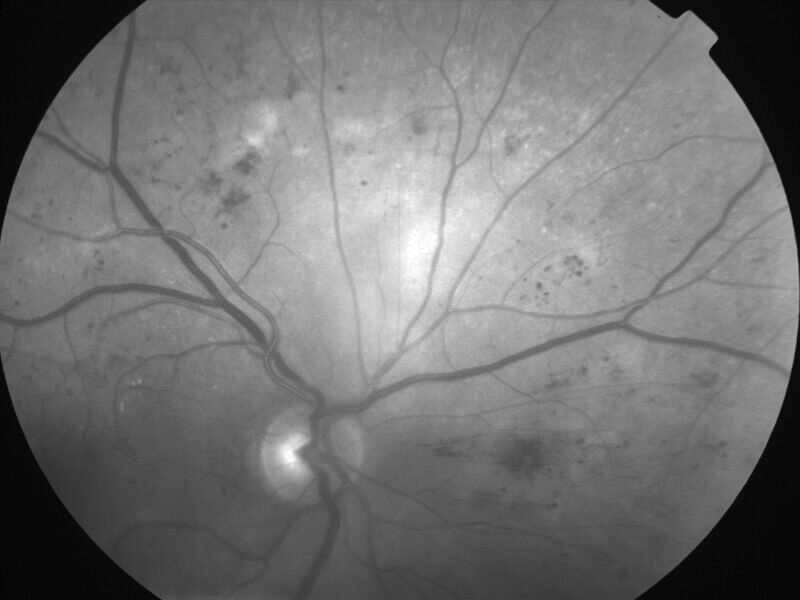

rétinopathie diabétique pré-proliférante

IM000006.jpg